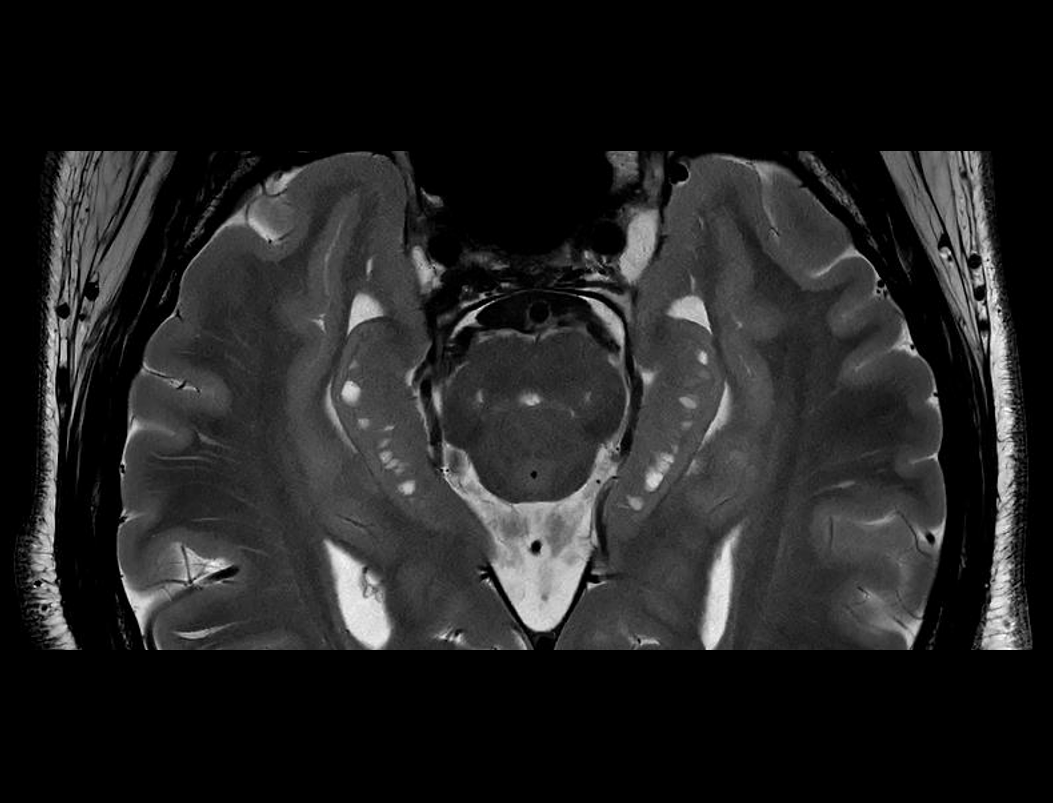

Galerie clinică

T2W FSE de înaltă rezoluție pentru hipocamp

Detectarea leziunilor mici de 2,2 mm